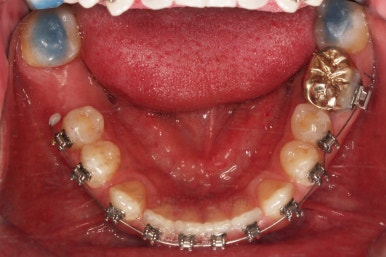

충치치료가 완료된 부위는 골드 크라운(금니)이 씌워졌어요.

임플란트를 하기에 적절한 사이즈로 공간은 맞춰줍니다.

임플란트는 언제 하게 되나요?

가장 많이 하시는 질문 중 하나인데요. 교정치료가 완료된 뒤에 임플란트를 하면 시간상 효율이 떨어져요.

임플란트는 뿌리 부분부터 머리 부분까지 완성되려면 몇 달의 시간 소요가 있을 수 있기 때문에 교정치료가 완료되기 몇 달 전인 즉, 임플란트 자리만 적절히 마련되면 임플란트를 하게 됩니다.

그 뒤에 임플란트의 완료와 교정치료의 완료가 동시에 되도록 시간세팅을 하면 환자분이 소모하는 시간이 가장 단축되죠.